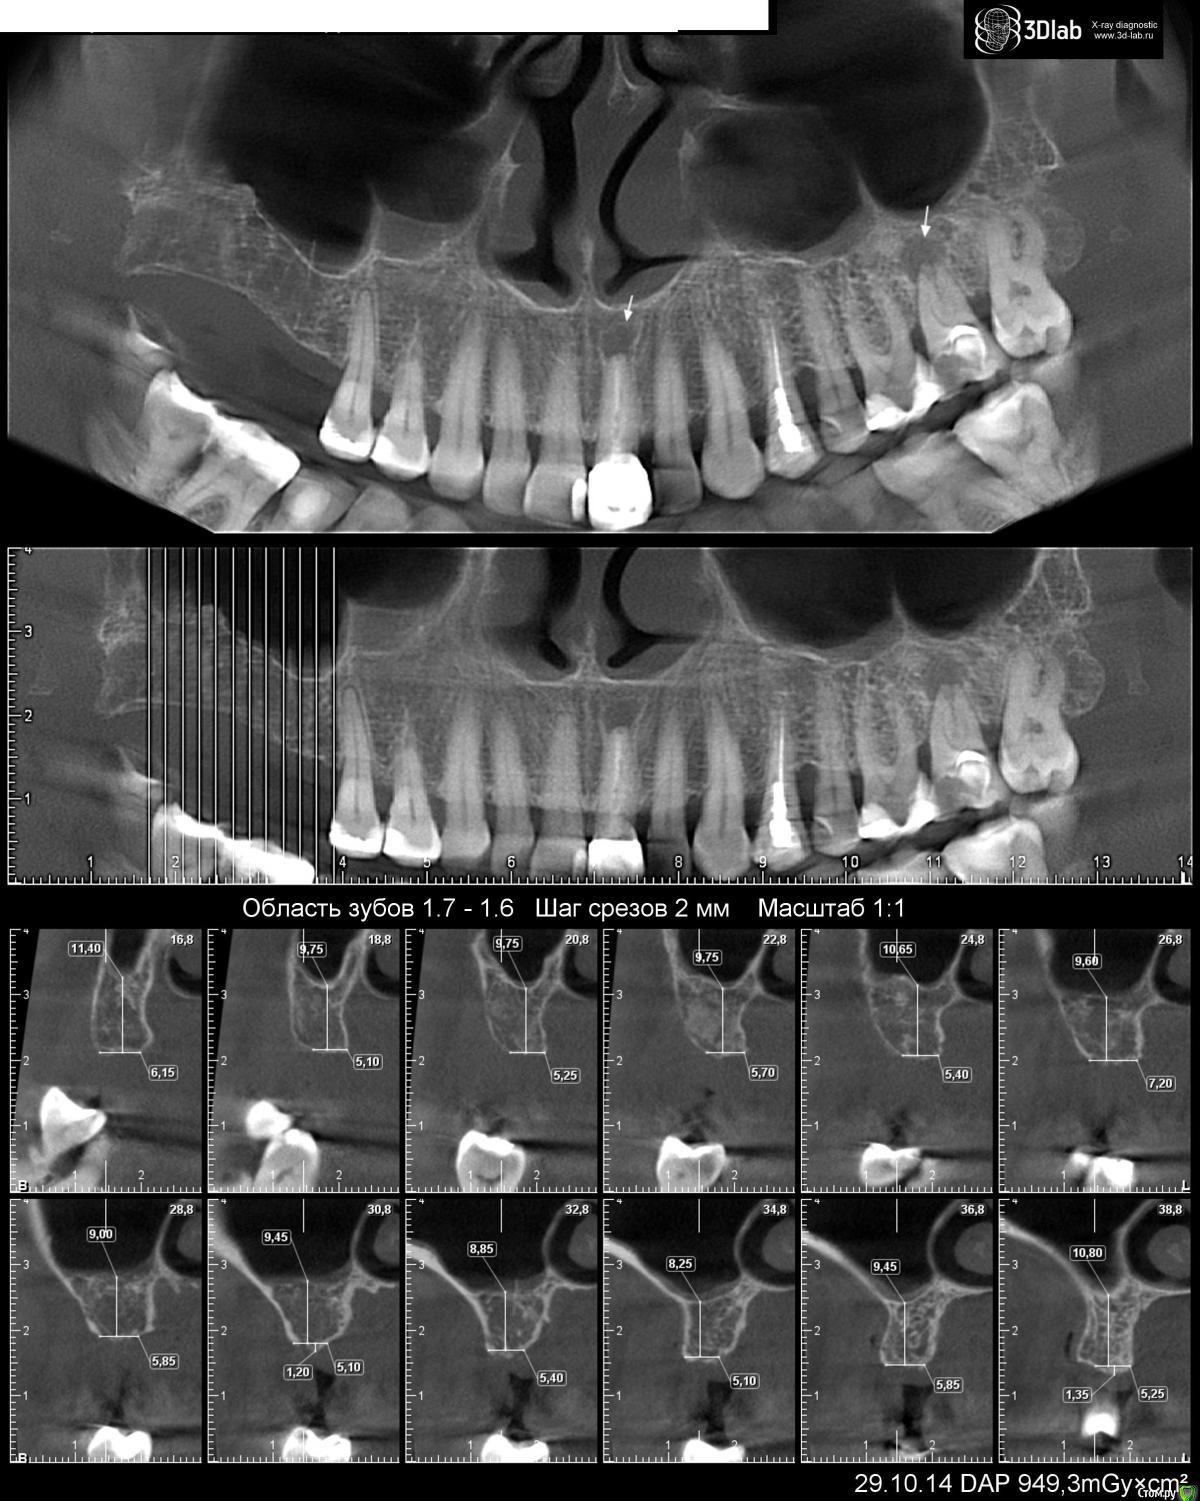

Trit Опубликовано 1 августа, 2015 Автор Поделиться Опубликовано 1 августа, 2015 Здравствуйте!Да, снимок есть, прилагаю. Ссылка на комментарий

red_butler Опубликовано 1 августа, 2015 Поделиться Опубликовано 1 августа, 2015 Замеры на снимке не корректные, условия для имплантации хорошие. Шаблон не обязателен. Если возможности позволяют - ставьте астру Ссылка на комментарий

red_butler Опубликовано 1 августа, 2015 Поделиться Опубликовано 1 августа, 2015 Могу только предположить, что речь о использовании имплантов разной длины. У астры ходовая длина 9 мм, у альфы 10, высота до дна синуса около 9 мм, 10 мм имплант пройдет либо с небольшим синуслифтом или с постановкой под углом. Ссылка на комментарий

stommm Опубликовано 1 августа, 2015 Поделиться Опубликовано 1 августа, 2015 Вы кт более 9 месяцев назад делали, за это время расстояние до пазухи могло и уменьшиться. Если размеры костной ткани актуальные, то имхо лучше астра 8-9 мм, но установленные в оптимальную для протезирования позицию. Ссылка на комментарий

AlexanderGudkov Опубликовано 2 августа, 2015 Поделиться Опубликовано 2 августа, 2015 Какие углы? У вас почти идеальные условия для имплантации. Сюда 8 или 9 мм ставить без всяких углов, наклонов и пр. Ссылка на комментарий